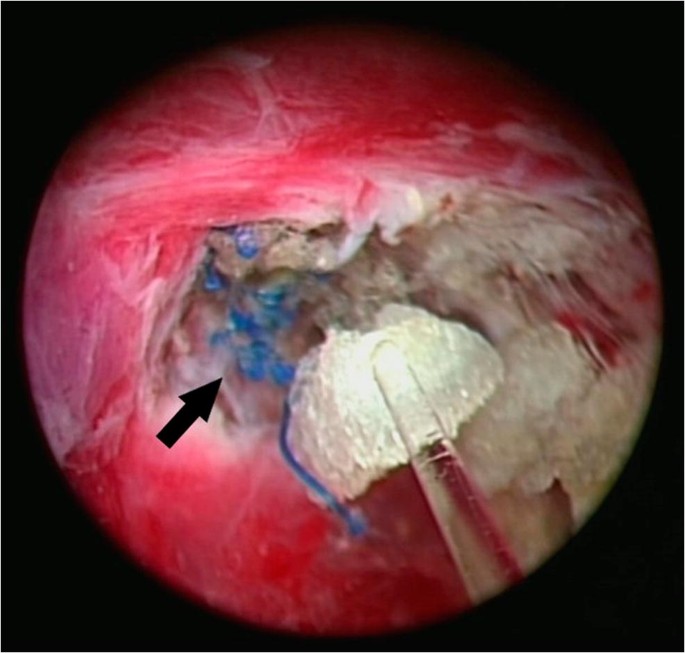

67-letni mężczyzna zgłosił się z nawracającą sepsą (posocznicą), obrzękiem w okolicy pachwiny i objawami dolnych dróg moczowych 12 lat po obustronnej naprawie przepukliny pachwinowej za pomocą metody laparoskopowej TEP. Diagnoza migracji (przemieszczenia siatki) i erozji w pęcherzu moczowym została postawiona za pomocą cystoskopii (wziernikowania pęcherza). Badanie okolicy pachwiny potwierdziło erozję siatki Prolene w bocznej ścianie pęcherza moczowego. Jest to drugi opisany przypadek po naprawie metodą TEP. Przegląd literatury ujawnia osiem opisanych przypadków po laparoskopowej naprawie od roku 1994. Omawiane są czynniki przyczyniające się do migracji i erozji siatki. W związku z coraz większą liczbą przypadków niestabilnej umocowania siatki opisywanych w literaturze światowej, możliwe jest, że w przyszłości wzrośnie częstość tej powikłania. Należy zachęcać do niższego progu diagnostycznego i raportowania tego powikłania.

żródło: Mesh erosion into the urinary bladder following laparoscopic inguinal hernia repair; is this the tip of the iceberg? Hernia. 2010 Jun;14(3):317-9. doi: 10.1007/s10029-009-0539-5. Epub 2009 Aug 6.